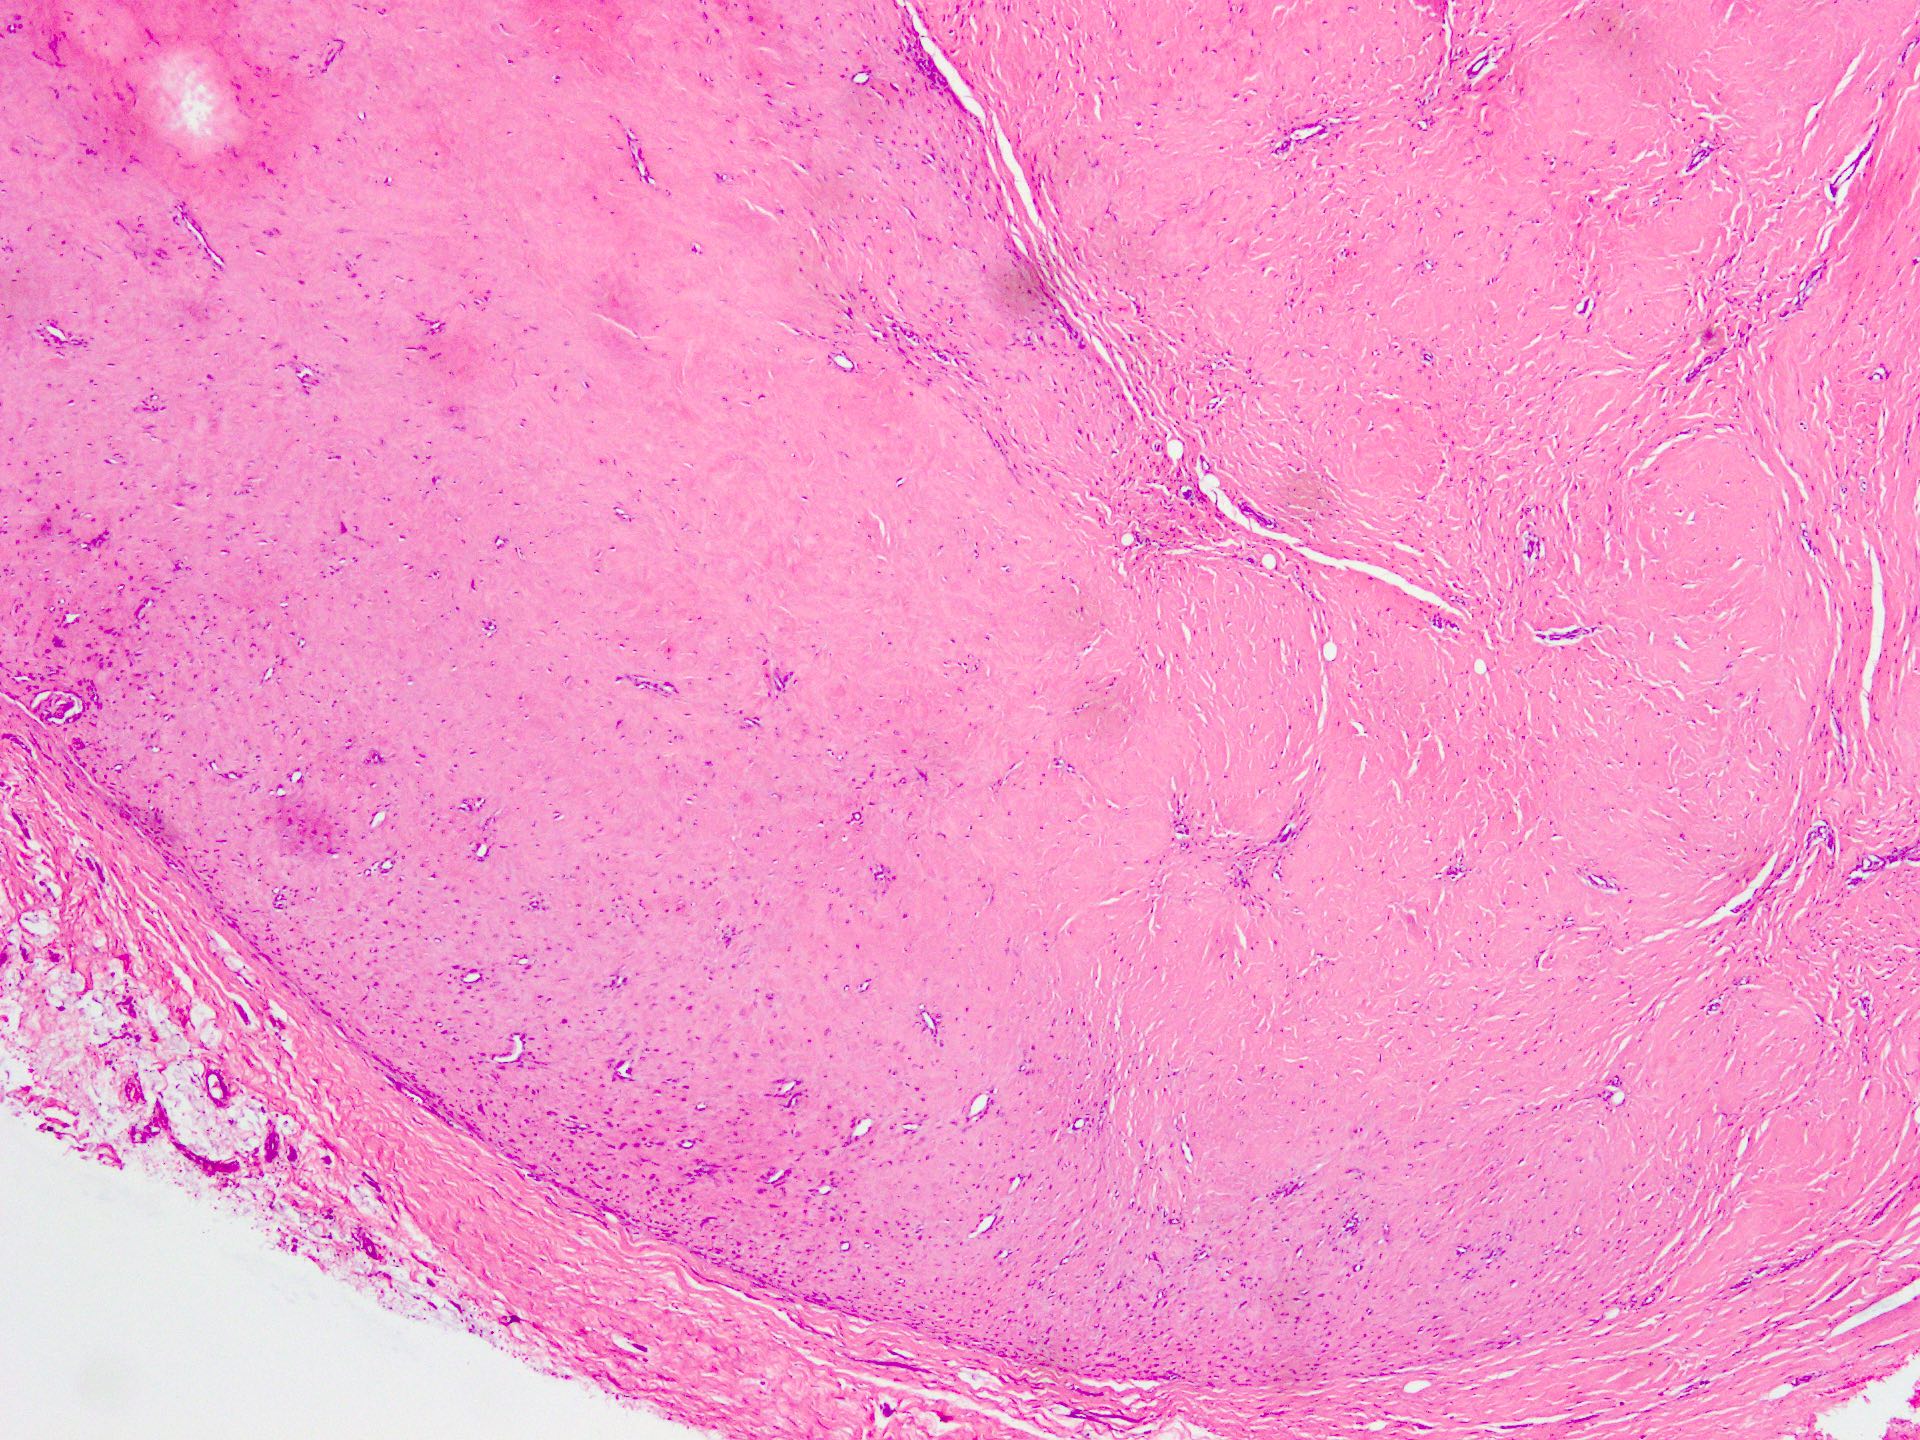

- Well circumscribed tumor of variable cellularity

- Cellularity mostly higher at tumor edges

- Bland spindle cells in a collagenous background

- Tumor has characteristic thin walled slit-like vessels

- Degenerative changes like myxoid / cystic change, osseous / chondroid metaplasia can be seen

- Bizarre pleomorphic cells can also be present

- Mitotically inactive

- Necrosis not present

- Cellular variant of fibroma of tendon sheath also exists; it overlaps morphologically with nodular fasciitis and fibrous histiocytoma (Cancer 1979;44:1945)

Contributed by Nasir Ud Din, M.B.B.S.

- Comment: Histology showed a well circumscribed, variably cellular lesion composed of bland spindle cells having regular nuclei arranged in sheets and fascicles. Thin walled vessels are present. The background is collagenous.

A 32 year old man has had painless swelling in the palm of his hand for 6 months. It was excised and the histology is shown in the above image. What is the most likely diagnosis?